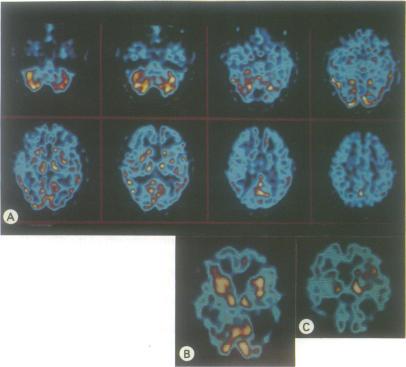

Thirty five patients with dementia of the Alzheimer type (DAT) and 35 controls matched for age, sex and handedness were investigated using single photon emission computer tomography (SPECT) with 99m technetium HMPAO. Regional cerebral blood flow (rCBF) was assessed semi-quantitatively in 18 cortical and 4 subcortical areas by normalising mean information density in each region to cerebellar mean information density. Analysis revealed significantly reduced rCBF to temporal, parietal, frontal and left occipital cortex in the patients whilst blood flow to subcortical areas showed no differences between the 2 groups. In addition, significant left-sided cortical hypoperfusion was seen in the DAT group but not in controls. When patients were sub-divided on the basis of disease severity, those with mild disease showed temporal, parietal and left frontal changes with more severely affected patients also showing right frontal and left occipital involvement. rCBF patterns did not distinguish between presenile and senile onset cases once duration and severity of illness were controlled. Eight cortical areas were also rated visually for perfusion deficits on a simple 4 point scale. Perfusion deficits were detected in 34 of 35 patients but in only 4 of 35 controls. In the DAT group significant correlations were found between many of the neuropsychological tests used and rCBF. Memory correlated with left temporal activity, praxis, perception, object assembly and block design with right parietal activity and language with activity throughout the left hemisphere. Significant correlations were also seen between subcortical and cortical blood flow, possibly explaining the correlations observed between many of the neuropsychological tests and thalamic blood flow.

对35例阿尔茨海默型痴呆(DAT)患者以及35例在年龄、性别和利手方面与之匹配的对照者,使用锝-99m六甲基丙烯胺肟(99mTc-HMPAO)单光子发射计算机断层扫描(SPECT)进行研究。通过将每个区域的平均信息密度与小脑平均信息密度进行归一化,对18个皮质区域和4个皮质下区域的局部脑血流量(rCBF)进行半定量评估。分析显示,患者颞叶、顶叶、额叶和左侧枕叶皮质的rCBF显著降低,而两组皮质下区域的血流量无差异。此外,DAT组出现显著的左侧皮质灌注不足,而对照组未出现。当根据疾病严重程度对患者进行细分时,轻度疾病患者表现出颞叶、顶叶和左侧额叶的变化,病情更严重的患者还表现出右侧额叶和左侧枕叶受累。一旦控制了病程和疾病严重程度,rCBF模式无法区分早老性和老年性发病病例。还使用简单的4分制对8个皮质区域的灌注缺损进行视觉评分。35例患者中有34例检测到灌注缺损,而35例对照者中只有4例检测到。在DAT组中,发现所使用的许多神经心理学测试与rCBF之间存在显著相关性。记忆力与左侧颞叶活动相关,运用、感知、物体组装和积木设计与右侧顶叶活动相关,语言与整个左侧半球的活动相关。皮质下和皮质血流量之间也存在显著相关性,这可能解释了许多神经心理学测试与丘脑血流量之间观察到的相关性。